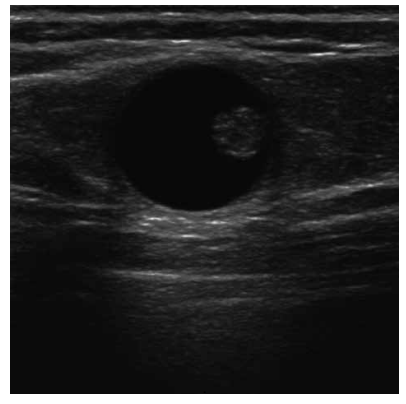

Analise o caso a seguir para responder às questões de 30 a 32.

Uma paciente de 52 anos realiza ultrassonografia de mamas de rotina. O exame evidencia uma alteração focal na mama esquerda, conforme mostrado na figura a seguir:

Qual a hipótese mais provável para o caso?